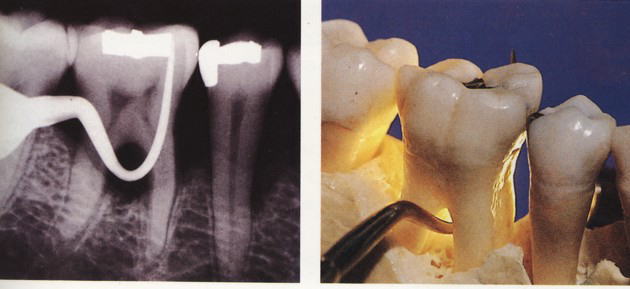

『ラ タイチャークの図版』より

多くの場合は歯周病の一つの病形で、歯周病一般の原因と同様、歯に付着した細菌性プラーク(デンタルバイオフィルム)によって惹き起こされる炎症性の感染症です。辺縁歯肉(ポケットの元の形である歯肉嚢の入り口)のブラッシングが不十分であったためプラークが形成され、歯根面を覆っていた歯槽骨が次第に吸収され、歯根分岐部が歯肉の中で露出している様態にあります。 2 根分岐部病変の症状

治療法としては様態に応じて、スケーリング・ルートプレーニング・分岐部入り口の整形によって磨きやすい形態を作る→歯槽骨の整形→歯根に対する処置(いずれかの根を抜歯する・複数の根の間を分割するなど)やトンネルの形成などの処置があります。 また「再生療法」として薄い皮膜を用いて歯槽骨の再生を誘導する『組織再生誘導法(GTR法)』や特殊な薬剤を用いる『エムドゲイン法』などがあります。 |